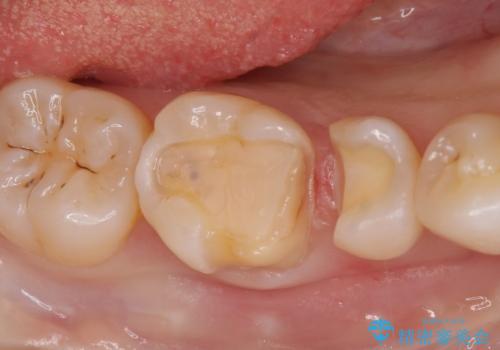

劣化した保険の詰め物部分の治療をしたい。

- 過去の樹脂の治療の劣化を治したいとの事で来院。大臼歯の歯は樹脂の範囲が大きくセラミックインレーで処置しても割れてしまう可能性があるため被せ物のご案内をしたところ、なるべく歯を削りたくないとのことでPGAアンレー(ゴールドアンレー)での治療となりました。手前の歯はセラミックの詰め物で治療する事ができました。

歯質の削除量をなるべく最小限にして治療が終わりました。

セラミック、ゴールド共に適合が良く虫歯の再発のリスクが低くなります。